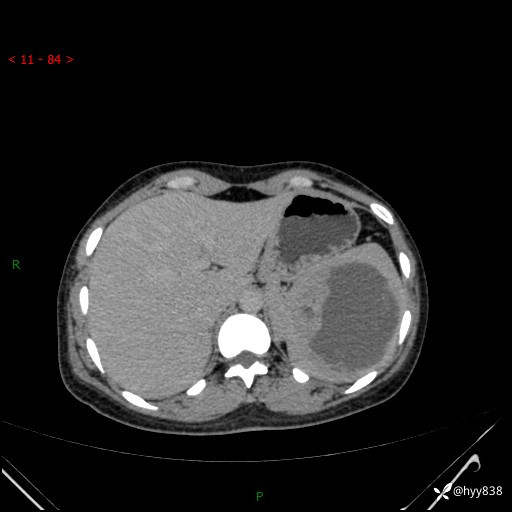

患者性别:男

患者年龄:44岁

主诉:外院超声发现脾脏占位,来我院进一步诊治。

辅助检查:CT

临床诊断:脾脏占位

脾脏CT平扫+增强(动脉期+静脉期)